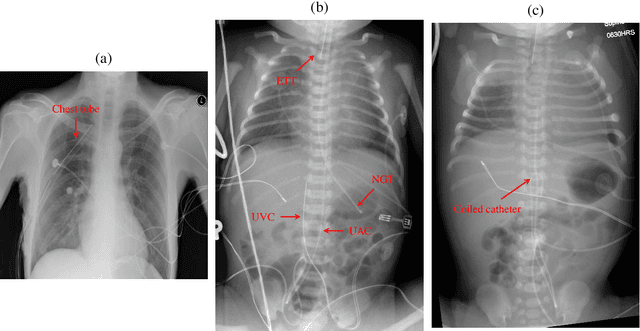

Abstract:We develop and evaluate a deep learning algorithm to classify multiple catheters on neonatal chest and abdominal radiographs. A convolutional neural network (CNN) was trained using a dataset of 777 neonatal chest and abdominal radiographs, with a split of 81%-9%-10% for training-validation-testing, respectively. We employed ResNet-50 (a CNN), pre-trained on ImageNet. Ground truth labelling was limited to tagging each image to indicate the presence or absence of endotracheal tubes (ETTs), nasogastric tubes (NGTs), and umbilical arterial and venous catheters (UACs, UVCs). The data set included 561 images containing 2 or more catheters, 167 images with only one, and 49 with none. Performance was measured with average precision (AP), calculated from the area under the precision-recall curve. On our test data, the algorithm achieved an overall AP (95% confidence interval) of 0.977 (0.679-0.999) for NGTs, 0.989 (0.751-1.000) for ETTs, 0.979 (0.873-0.997) for UACs, and 0.937 (0.785-0.984) for UVCs. Performance was similar for the set of 58 test images consisting of 2 or more catheters, with an AP of 0.975 (0.255-1.000) for NGTs, 0.997 (0.009-1.000) for ETTs, 0.981 (0.797-0.998) for UACs, and 0.937 (0.689-0.990) for UVCs. Our network thus achieves strong performance in the simultaneous detection of these four catheter types. Radiologists may use such an algorithm as a time-saving mechanism to automate reporting of catheters on radiographs.

Abstract:Catheters are the second most common abnormal finding on radiographs. The position of catheters must be assessed on all radiographs, as serious complications can arise if catheters are malpositioned. However, due to the large number of radiographs performed each day, there can be substantial delays between the time a radiograph is performed and when it is interpreted by a radiologist. Computer-aided approaches hold the potential to assist in prioritizing radiographs with potentially malpositioned catheters for interpretation and automatically insert text indicating the placement of catheters in radiology reports, thereby improving radiologists' efficiency. After 50 years of research in computer-aided diagnosis, there is still a paucity of study in this area. With the development of deep learning approaches, the problem of catheter assessment is far more solvable. Therefore, we have performed a review of current algorithms and identified key challenges in building a reliable computer-aided diagnosis system for assessment of catheters on radiographs. This review may serve to further the development of machine learning approaches for this important use case.

Abstract:Catheters are commonly inserted life supporting devices. X-ray images are used to assess the position of a catheter immediately after placement as serious complications can arise from malpositioned catheters. Previous computer vision approaches to detect catheters on X-ray images either relied on low-level cues that are not sufficiently robust or only capable of processing a limited number or type of catheters. With the resurgence of deep learning, supervised training approaches are begining to showing promising results. However, dense annotation maps are required, and the work of a human annotator is hard to scale. In this work, we proposed a simple way of synthesizing catheters on X-ray images and a scale recurrent network for catheter detection. By training on adult chest X-rays, the proposed network exhibits promising detection results on pediatric chest/abdomen X-rays in terms of both precision and recall.